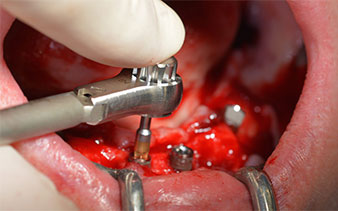

El siguiente ajuste programado es la propia inserción de los implantes. En nuestra clínica, solemos insertar los implantes con una fuerza de 32 Ncm de manera estándar (figs. 12 y 13).

El requisito imprescindible para el tratamiento inmediato es una alta estabilidad primaria. Para satisfacer dicho requisito, en este caso, se prescindió del corte de rosca. La unidad de accionamiento Implantmed de W&H empleada aquí, posee un modo propio para ello que también puede seleccionarse directamente y resulta imprescindible para muchas indicaciones. Los últimos giros para la inserción del implante superaron el valor de 32 Ncm, por lo que se realizaron manualmente. En tales casos, se recomienda utilizar la función autocortante de los implantes y girar el implante varias veces hacia delante y hacia atrás de forma que el implante se aproxime gradualmente hasta su posición definitiva sin ejercer una presión excesiva sobre el hueso (fig. 14).